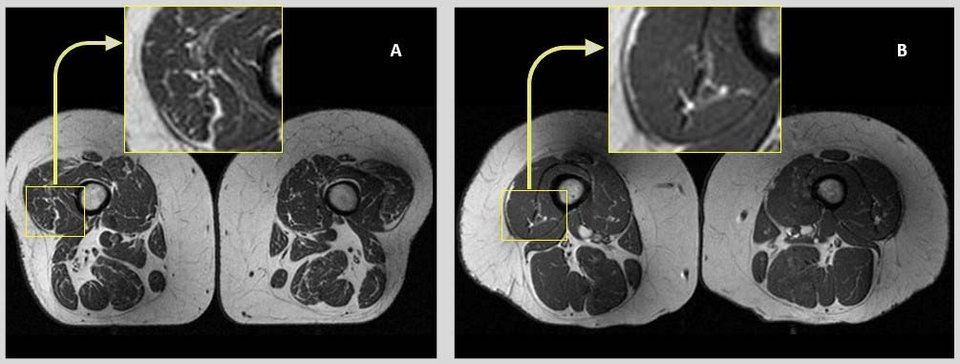

- Εικόνες μαγνητικής τομογραφίας από τις πλευρικές πτυχές των τετρακέφαλων μηριαίων μυών δύο γυναικών που συμμετείχαν στη μελέτη, ηλικίας 58 (Α) και 62 ετών (Β).

- Στη γυναίκα Α, της οποίας η διατροφή αποτελείτο κατά 68% από υπερεπεξεργασμένες τροφές, οι μηριαίοι μύες παρουσιάζουν πολλές λιπαρές ραβδώσεις.

- Στη γυναίκα Β, που η διατροφή περιείχε μόνο 36% υπερεπεξεργασμένα τρόφιμα, οι μύες των μηρών παρουσιάζουν λιγότερες λιπαρές ραβδώσεις.CREDIT: Radiological Society of North Aurora (RSNA) and Zehra Akkaya